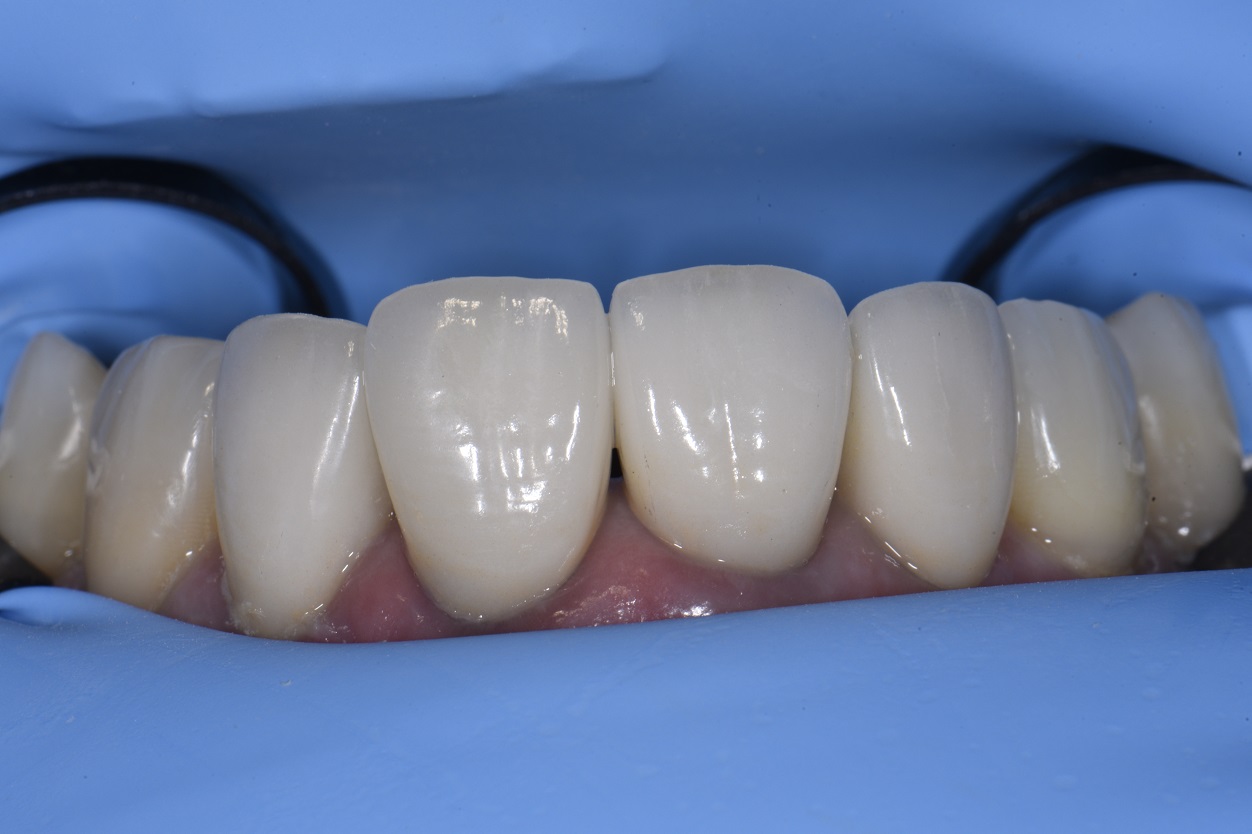

From www.clarencetam.co.nz

Workflow to Replace Two Old Crowns How Do They Remove An Old Crown The dentist will first numb the gums to reduce discomfort. An adhesive may also be used on the permanent crowns to weaken the cement. At times, the dentist may use the old crown if it is not severely damaged. Depending on a multitude of factors, that number will vary. If you suspect that your old dental crown needs to be. How Do They Remove An Old Crown.